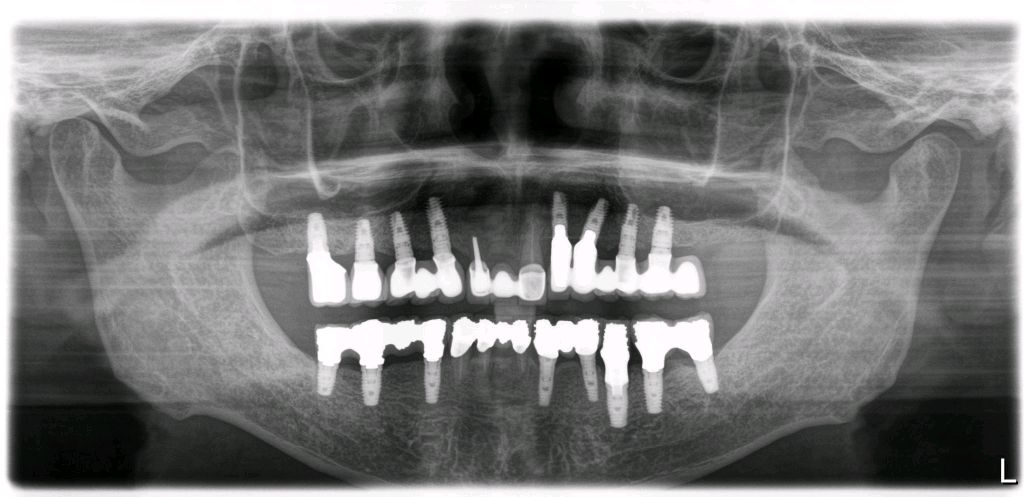

程先生,80岁种植牙复诊,共种了17颗牙,距离第一颗种植牙己定期随访15年,无松动疼痛等症状,用的很是满意。